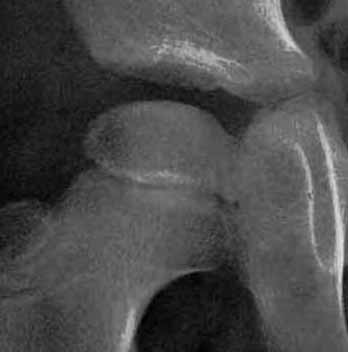

左図は手術前です。骨頭の外側の1部が臼蓋からはみだしています。右図のように骨切りをおこなって、骨頭の向きを変え、はみだした部分までも完全に臼蓋の奥深くに包み込みます。この手術は術前に骨の正確な計測を行い、手術ではその計画を厳密に実行します。皮膚切開の後には、筋肉の剥離、骨の展開、関節包の温存、金属の打ち込む方向、注意深い骨切り、下肢短縮を最小限に押さえる工夫、など、いずれをとっても慣れた術者が行わないと(少なくとも50例の経験は必要)重篤な合併症をおこすことがあります。

上図は10歳男子で、装具療法がうまくゆかないまま放置されていた例で、著しい変形があった例です。